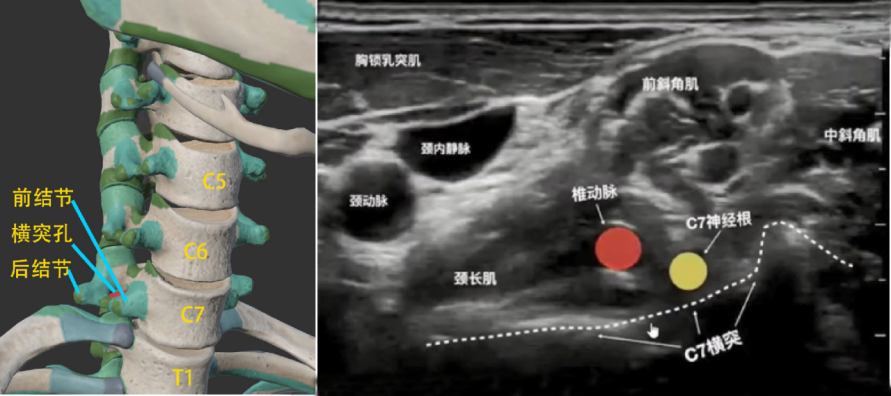

扫查方法:关键是寻找到C4颈椎位置,要找到C4颈椎,关键又是要找到C7颈椎,或体表找到甲状软骨上缘(平C4颈椎)。具体方法见本书最后一节的内容,在此提示颈椎骨定位的关键点是:C7呈“斜坡”、C6呈“手枪”、C5呈“大V”、C4呈“小V”。